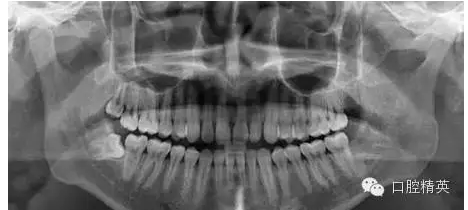

7、拔牙后全景片

診斷 : 下八近中中位阻生